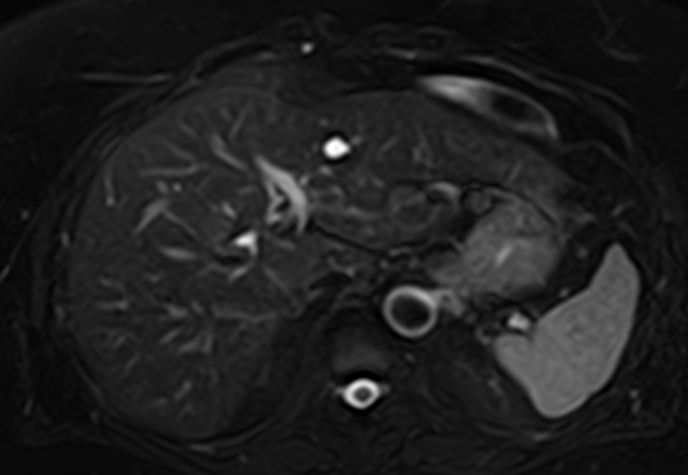

Магнитно-резонансная томография является современным наиболее информативным неинвазивным методом диагностики заболеваний печени. С помощью использования магнитного поля, обладающего высокой индукционной мощностью, МРТ позволяет получать послойные изображения органа и окружающих тканей и выявлять патологические изменения в печени на самых ранних стадиях развития, когда другие методы диагностики не дают результатов. Кроме того, процедура безболезненна и безопасна, так как организм не подвергается воздействию вредного рентгеновского излучения. Это позволяет назначать МРТ неоднократно в течение короткого промежутка времени, например, для оценки динамики состояния органа на фоне лечения.

В клинике «Доступная медицина» исследование проводится на современном высокопольном томографе экспертного класса TOSHIBA VANTAGE TITAN 1,5 Тесла. Аппарат послойно сканирует исследуемую зону в трех плоскостях с шагом от 1 мм, при этом получая данные о структуре органа в мельчайших подробностях. Инновационные компьютерные программы реконструируют данные в трехмерные модели органа, отображающие состояние не только паренхимы печени, но и внутрипеченочных желчных протоков и сосудистой системы.

Использование в процедуре МР-сканирования контрастирующих красителей позволяет выявить и охарактеризовать поражения печени размером от 1 мм, отличать доброкачественные и злокачественные новообразования, метастазы.

На томографических снимках хорошо заметны:

- доброкачественные очаговые поражения печени (гемангиома, очаговая узловая гиперплазия, гепатоцеллюлярная аденома, кисты (в том числе и паразитарные), липома, абсцесс, инфекции);

- злокачественные очаговые поражения печени;

- заболевания желчных протоков и желчного пузыря;

- диффузные болезни печени (стеатоз, воспалительные заболевания (вирусный гепатит, склерозирующий холангит), цирроз;

- патологии сосудов (тромбозы, артерио-венозные мальформации)

- рубцовые изменения после травм или операций